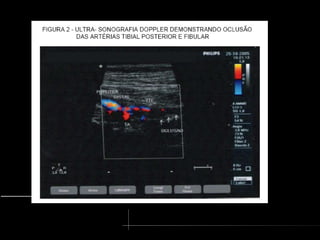

USG Duplex scan

•Não invasivo, mais empregado

•Identifica placas de ateroma e seus efeitos hemodinâmicos

•Examinador-dependente